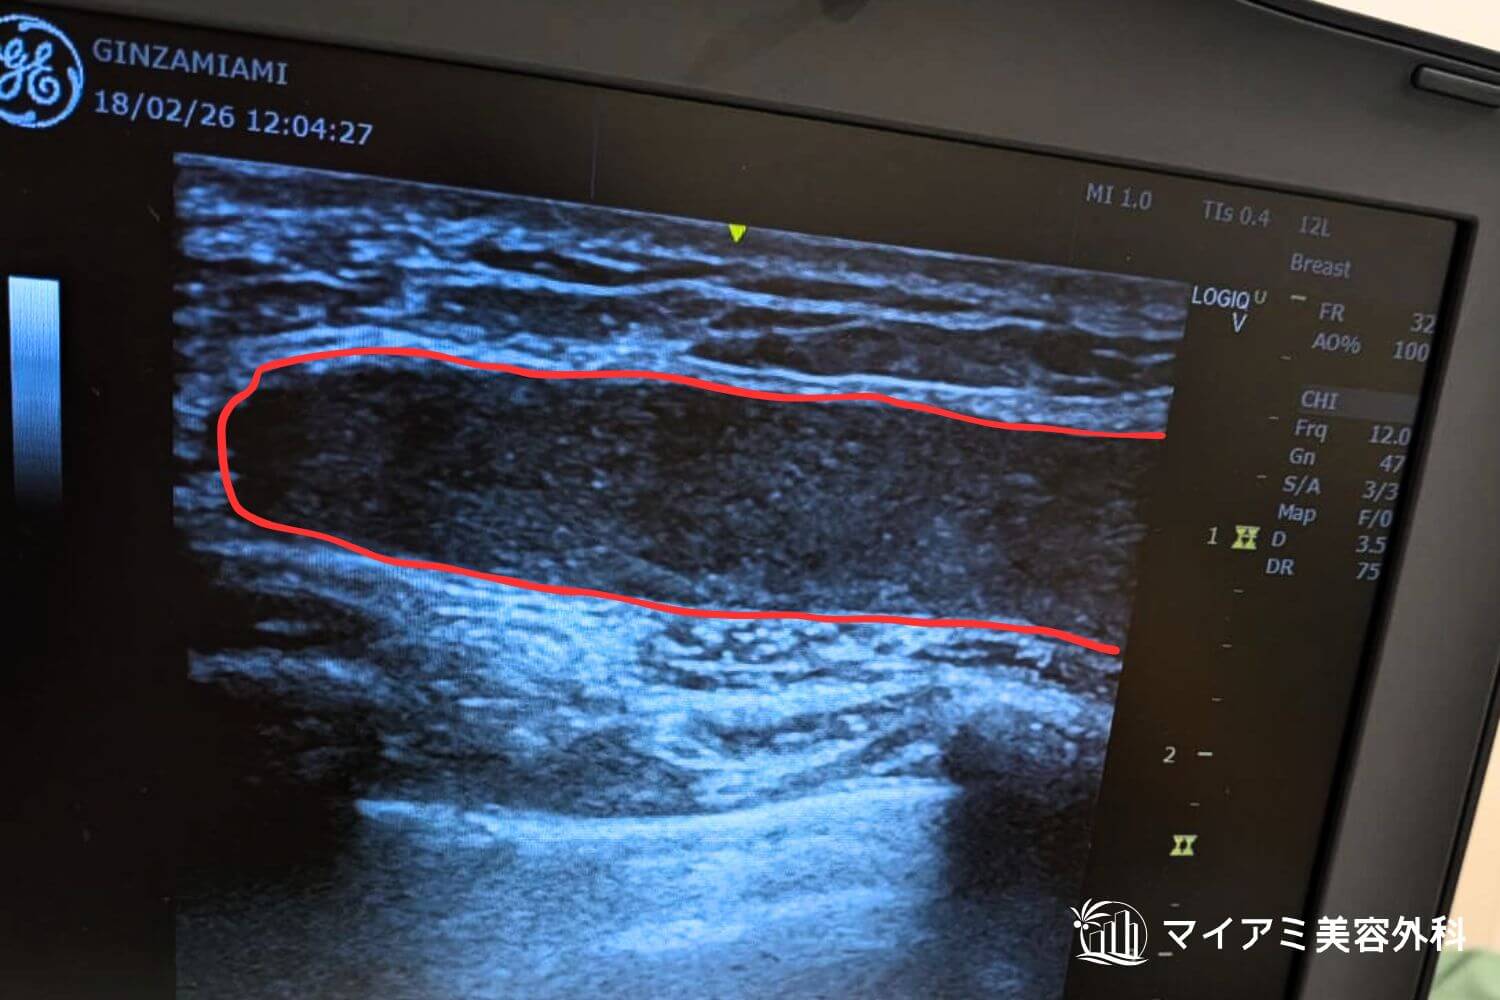

アクアフィリング除去を成功させるためには、製剤がどこに、どの程度広がっているかを術前に正確に把握することです。

当院では高性能なエコー(超音波)機器を駆使し、肉眼では確認できないフィラーの層やしこりの深さをミリ単位で特定します。

吸引前のエコー画像です。黒い溜まりがアクアフィリングです。

吸引後のエコー画像です。吸引後は厚みが数ミリに薄くなっています。